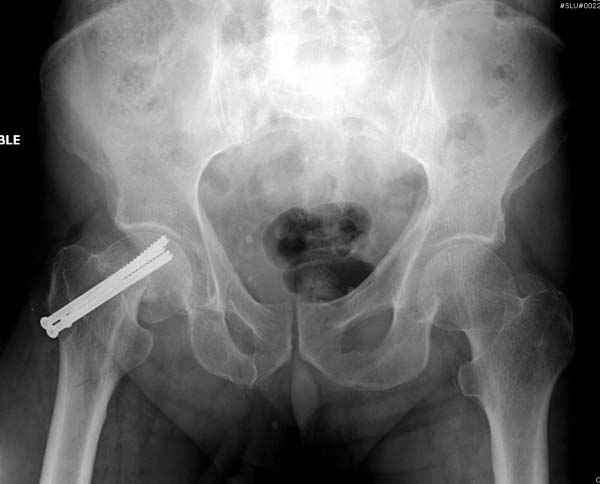

Профилактику дальнейшего раскола неполного перелома шейки провели тремя канюлированными шурупами.

На второй день после выписки упал дома. Снимки приложены. Коллеги рекомендуют удаление шурупа и вытяжение. Что делать?

Привет из солнечного Будапешта с Eurotrauma-2008. Да, замечательный пример. Получается, профилактику расхождения отломков шейки надо было проводить каким-то реконструкционным или проксимальным гвоздем, причем сразу длинной версией. Сейчас, наверно, так и надо бы сделать.

Убрать винты, каким-то джойстиком в вертельной области сделать репозицию шейки, фиксировать ее спицами, а дальше вправлять и фиксировать как вертельный перелом.

Решайте проблемы по мере поступления. На первом этапе решение одно, и на мой взгляд верное. Ситуация изменилась кардинально - другое решение. Я бы избрал ресинтез, убрав винты заменил на Гамму. Что с ним будет послезавтра? - Будем решать послезавтра. Такая наша доля.